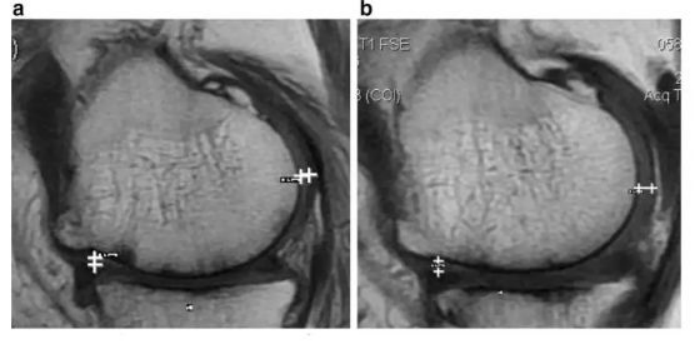

`研究结果:治疗后,,,2年后WOMAC评分也得到改善。。。6分钟内步行距离也显著增加。。。60%的病人的软骨体积增加。。

如上图所示,,,,左图为治疗前,,,,右图为治疗后,,,白色“+”处示意软骨增厚。。